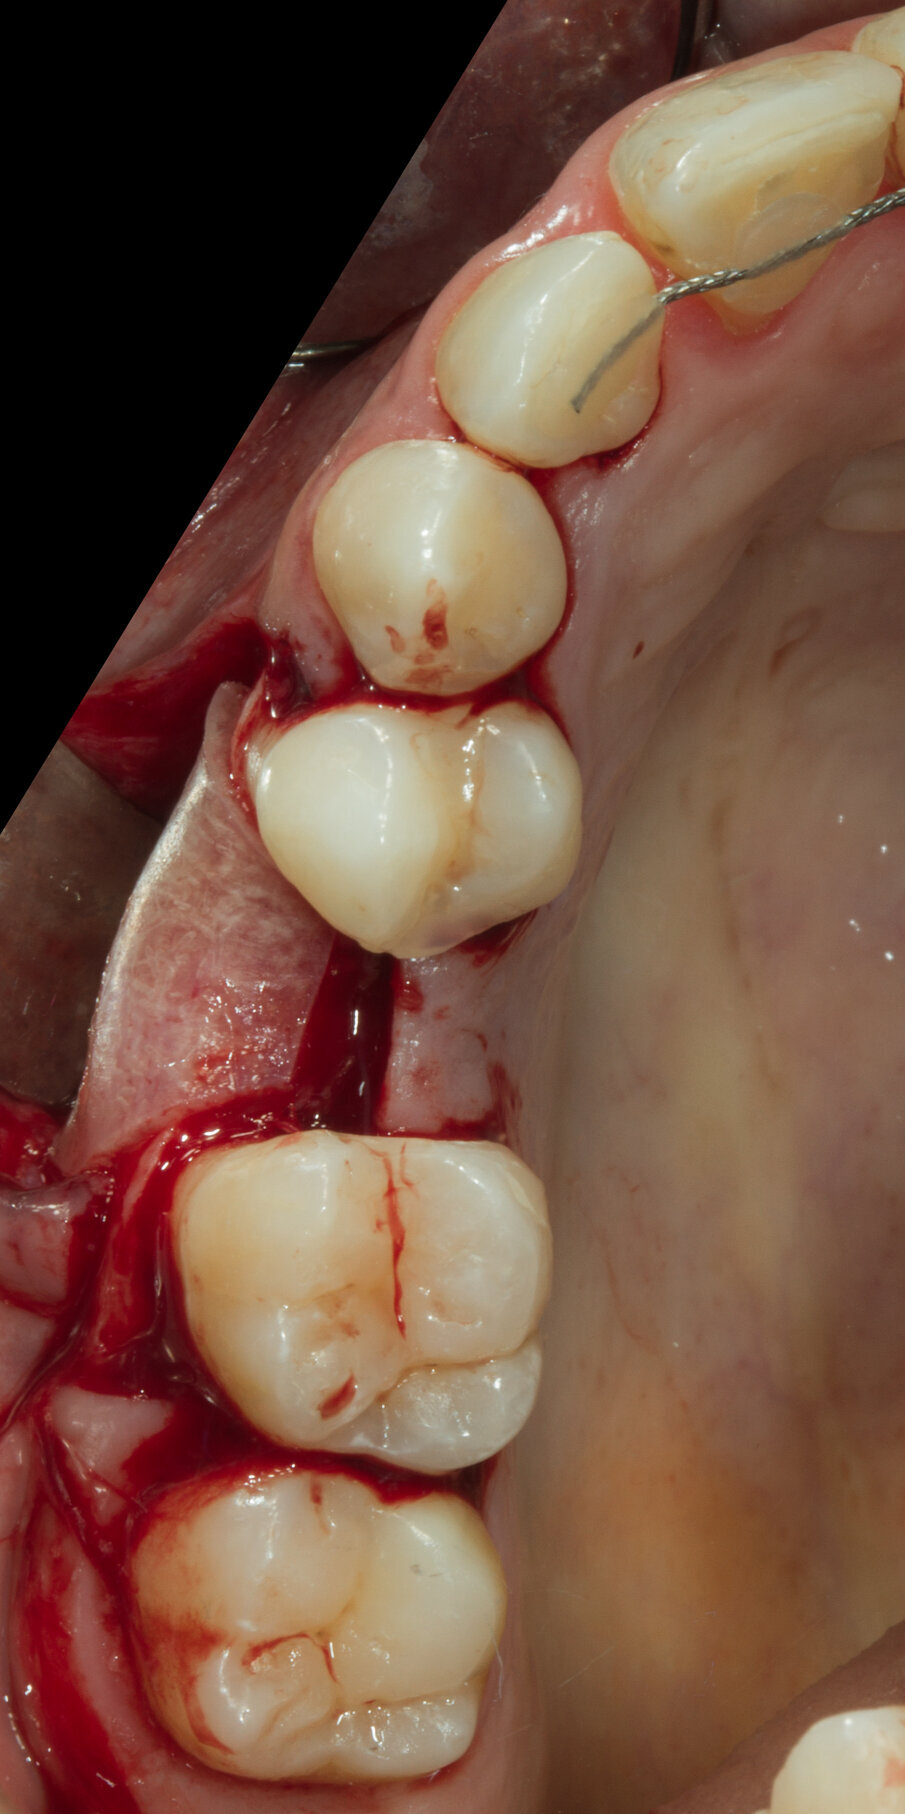

Si programma un intervento di GBR con rigenerazione ossea orizzontale mediante utilizzo di granuli di sostituto osseo eterologo (OsteoBiol Gen-Os) e un device riassorbibile costituito da osso corticale eterologo (OsteoBiol Lamina Soft). A 10 mesi verrà inserito un impianto differito. Dopo aver inciso un lembo mucoperiosteo con incisioni di scarico verticali e scollato sino alla parte più apicale del vestibolo si apprezza l’estrema sottigliezza della cresta residua e la sua corticalizzazione (Figg. 5, 6). Vengono praticati dei fori di 1,4 mm di diametro nella corticale vestibolare per esporre la midollare interna e aumentare la vascolarizzazione del particolato osseo che verrà innestato nel difetto osseo (Fig. 7).

Fig. 5 - Il marcato avvallamento osseo è presente in tutta l’altezza del vestibolo.

Fig. 6 - Visione crestale del difetto osseo.

Fig. 7 - Visione vestibolare del difetto osseo.

Dopo aver passivizzato il lembo si esegue una sutura a materassaio orizzontale e punto staccato centrale sulla parte crestale e suture semplici sulle incisioni di scarico (Figg. 13, 14). Dopo 10 mesi di guarigione si può procedere all’intervento di posizionamento implantare (Figg. 15-17). Sia dalle fotografie a lembo aperto (Figg. 18, 19) e da quelle di confronto tra la situazione alla baseline e dopo rigenerazione della cresta ossea (Figg. 20, 21) si può valutare come si sia ricostituito un osso ben corticalizzato, vascolarizzato, che ha riempito tutto il difetto osseo preesistente.

Fig. 18 - Ricostruzione completa del Bone Housing.

Fig. 19 - Visione vestibolare.